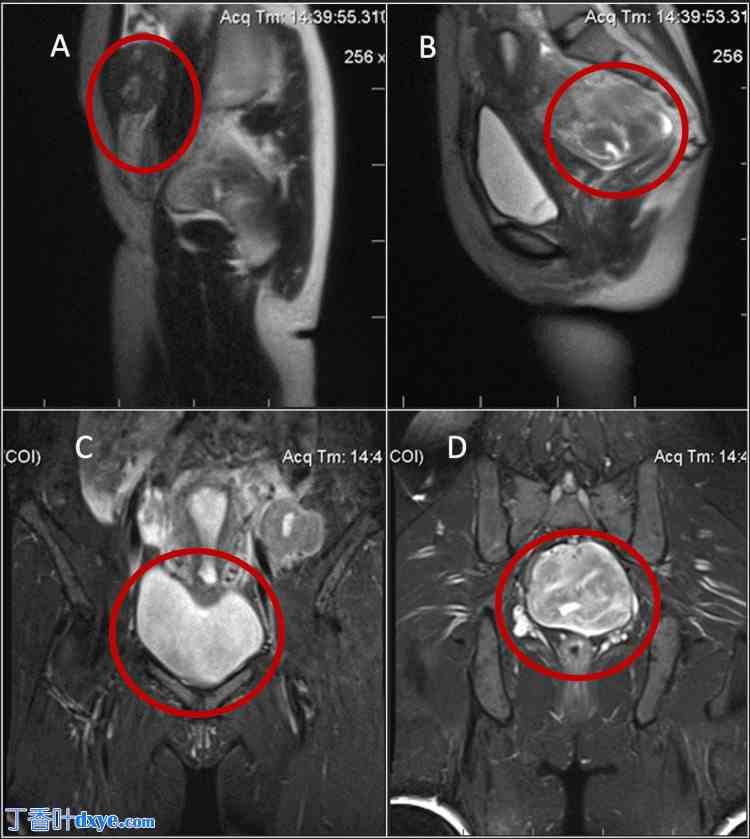

妇科检查发现子宫增大,大小与孕12周时相当。MRI检查显示,T1加权像(T1WI)和T2加权像(T2WI)上均可见信号强度与骨骼肌和平滑肌相似的肿块(图1)。

图1. 腹壁内可见一个信号强度与肌瘤相似的肿块(A)。子宫后壁可见一个异常肿块,大小约为90x68x95毫米。肿块边界清晰,信号强度与子宫肌层相似,并压迫直肠(B)。注射造影剂后,肿块呈强而均匀的强化(C)。在左卵巢下方,检测到一个尺寸为52x43x54毫米的类似肿块(D)。